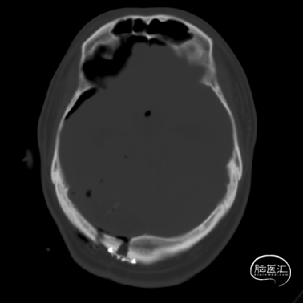

术前MRI检查提示左侧丘脑中脑海绵状血管瘤并卒中,梗阻性脑积水;

诊断:1.左侧丘脑中脑海绵状血管瘤并卒中,2.梗阻性脑积水;

年轻患者,较短时间内发生左侧丘脑二次出血,出现右侧面部及上肢麻木,复视,第二次出血后并发梗阻性脑积水,出现头痛。结合病史、神经系统体征、头颅CT及MRI检查,诊断左侧丘脑及中脑CM并卒中、脑积水明确,并导致了神经功能障碍,具备手术指征。

本例患者磁共振检查清晰显示病变位于左侧丘脑中脑区域,且位于丘脑内下方向中脑顶盖延续,病变的上部、前部、外侧部都有重要的神经组织,因此,手术从上方、前方、外侧方向切除病变均难以实施;